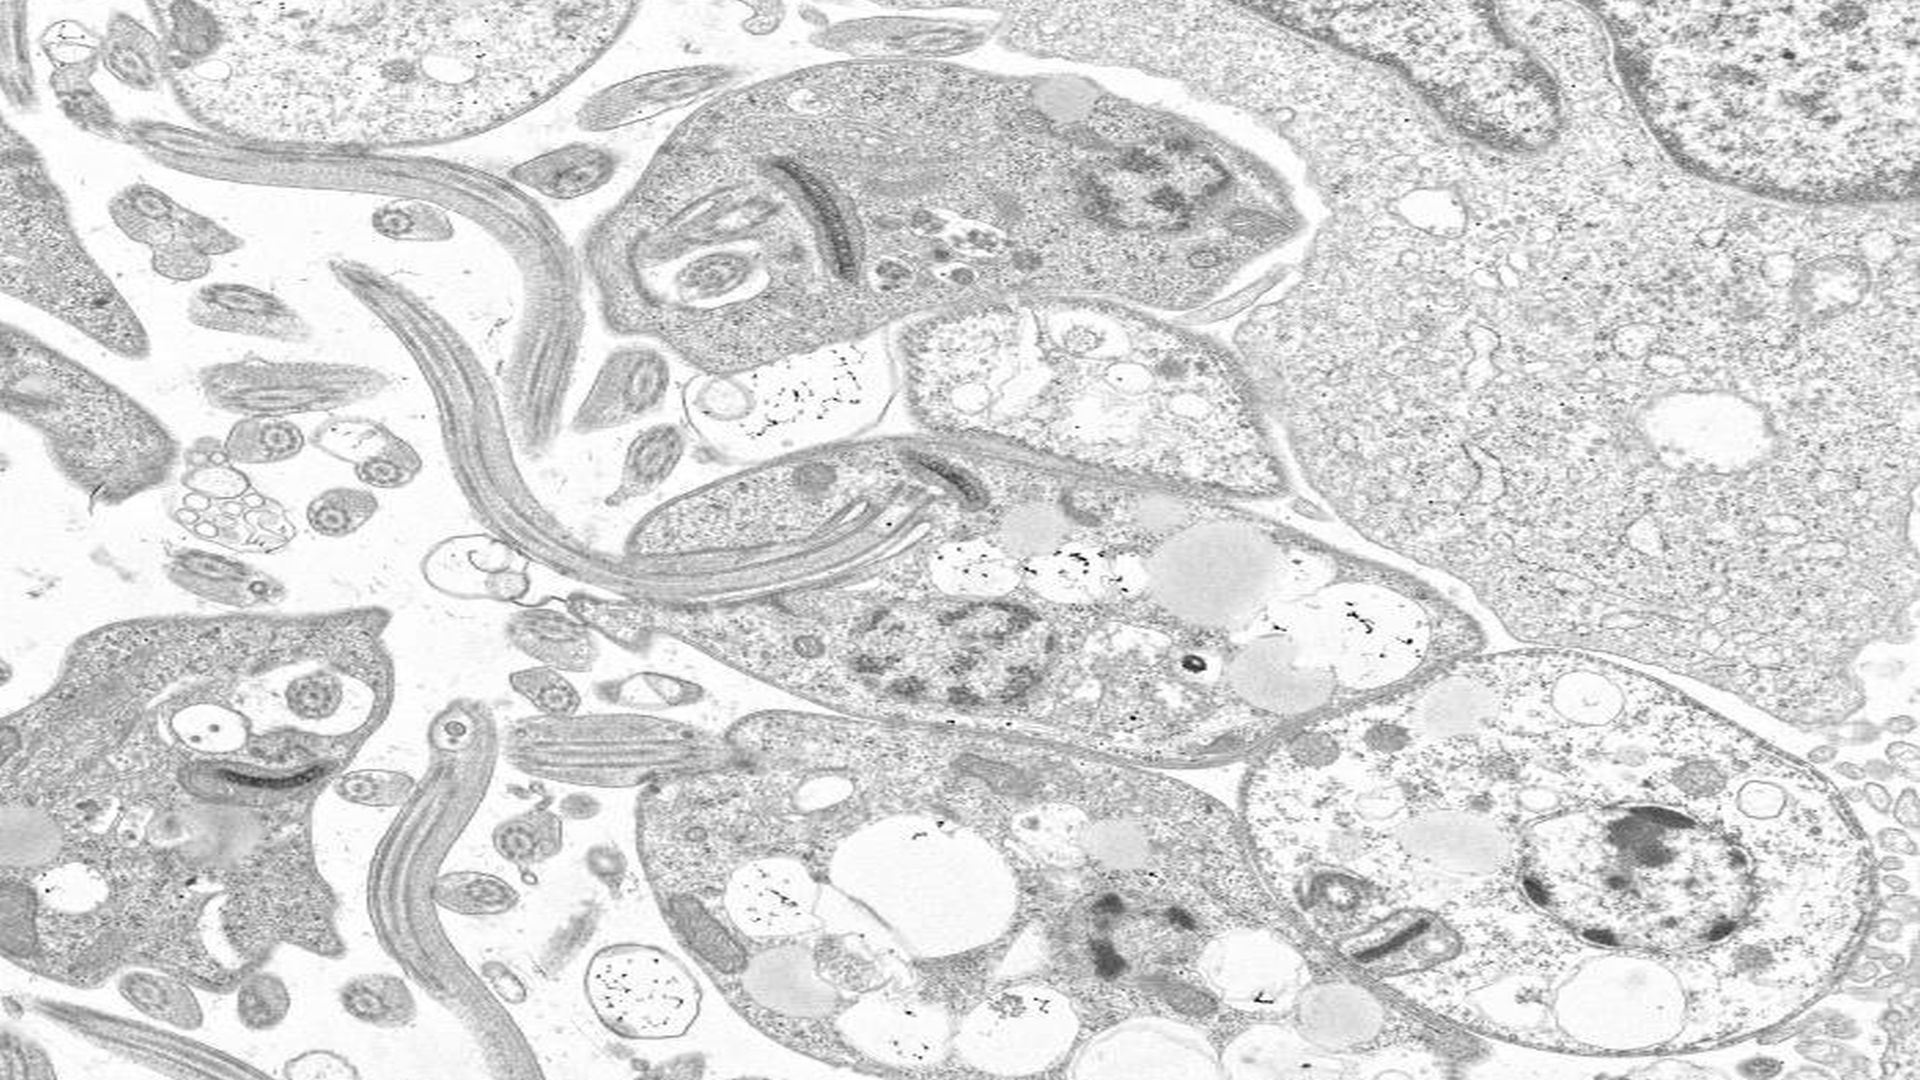

Now, mathematicians, experimental biologists and immunologists have revealed a 'patchy landscape of parasites' found on carriers' skin that determines how many parasites are picked up by sand flies.

Using mathematical modeling, they showed that some areas of skin can contain particularly high numbers of the parasite, while other areas may not. This means that whether a sand fly becomes infected or not depends on where they bite a person.